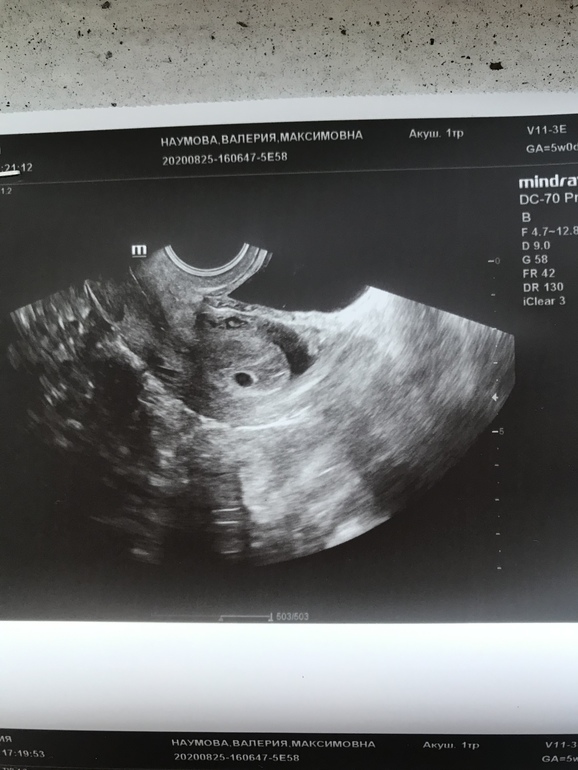

Срок по м ровно 5 недель По пя 5+3

У вас плодное яйцо всего 6 мм. Конечно, там еще ничего не видно 🤗 у меня в 5, 3 недель пя было 5мм и всё, через 1,5 недели уже и малыш 3,4мм, и жм 3мм, и чсс 106.

🤦🏼♀️🤦🏼♀️🤦🏼♀️ Боже какой бред ваш врач говорит. Вообще то могут заподозрить анэмбрионию если нет эмбриона в ПЯ больше 16мм, а подтвердить если его нет в ПЯ 25мм. У вас только 6мм ПЯ! Мне интересно какого размера эмбриона она там хотела найти? На сроке всего 5 недель. Девушка, у вас все в порядке, не переживайте, даже в 6 недель не всегда находят эмбрион. Переделайте узи в 7 полных недель, там уже точно все найдут)))